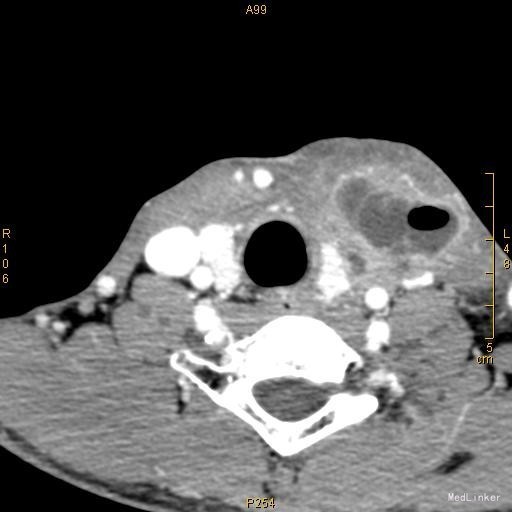

查体:颈前有明显手术瘢痕,左侧颈外侧区可触及一约3cm×3cm大小肿物,质韧,边界不清,表面光滑,不可随吞咽上下移动,触痛明显,颈部未闻及明显血管杂音。 辅查:2015-11-16我院颈部增强CT示左侧颈部感染,多发脓肿形成。

该患者在诊断上是有些困难,颈部多发脓肿是明确的,但是瘘口的位置不好确定,从而未能确诊,8年前患者行上消化道钡餐检查,诊断“食管瘘”,但是我们从8年前的影像上看,瘘口的位置太高,不像是食管的瘘口,考虑是不是梨状窝的瘘道,为了进一步确诊,我们给患者行了胃镜检查,结果胃镜发现左侧梨状窝有1个3mm大小的小孔,胃镜未能通过,食管未见明显的瘘口。为了更加明确瘘口的位置,我们与影像科商议后决定口服造影剂后行颈部CT平扫,因怕钡餐沉积在脓肿内不好排出,我们采用了口服碘化油。此次影像明确了瘘口的确在左侧梨状窝。最终诊断:左侧颈部多发脓肿;左侧梨状窝瘘道形成。 治疗:入院后予抗感染、禁食、营养支持等治疗,患者感染得以控制,请耳鼻咽喉科会诊后建议转科治疗。